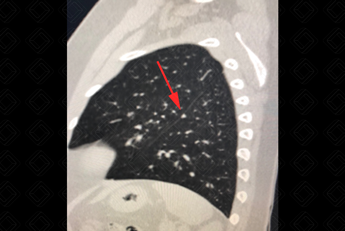

Texto alternativo para a imagem Figuras 1 e 2. Créditos: Dra. Elazir Mota - Rio de Janeiro/RJ

Descrição das figuras 1 e 2: Linfonodos intrapulmonares nas cissuras oblíquas direita e esquerda (setas vermelhas). [cms-watermark]

Algumas características tomográficas do tórax podem auxiliar no reconhecimento do linfonodo intrapulmonar:

• Esses linfonodos são ovais, redondos, triangulares ou trapezoidais, com bordas bem definidas;

• Localizam-se quase sempre abaixo do nível da carina, predominantemente nas regiões subpleurais dos lobos inferiores;

• Frequentemente estão aderidos à pleura ou separados da superfície pleural por alguns milímetros;

• Os linfonodos intrapulmonares têm aderências finas e lineares que se estendem do nódulo até a pleura (vide imagens).